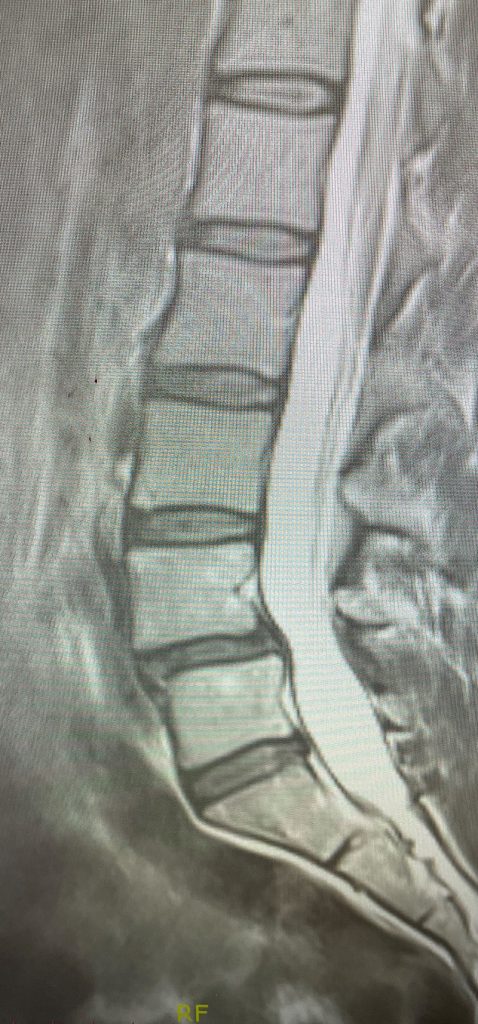

This 42-year-old female presents with ten years of progressive low back pain and leg pain. She had mild left dorsiflexion and EHL weakness. She had tried physical therapy, but her symptoms persisted. MRI revealed an L4-5 grade 1 spondylolisthesis with stenosis (Fig 1). We discussed options. We decided to try an epidural injection and continue with physical therapy. She will follow up with me in 6-8 weeks to see how she is doing with her pain and strength.

My thinking is that if she has no significant improvement, I would give her the option of going to a chiropractor or getting acupuncture. Ultimately, if she does not improve over the next couple of months, where her quality of life is affected or she has progressive weakness, surgery will be offered.

An L3-5 laminectomy would be offered with an extensive facetectomy to fully decompress bilaterally her L4 and L5 nerve roots and perform a posterolateral fusion with titanium screws to fixate her level to prevent further instability and to prevent recurrent stenosis. Because of her relative disc height loss and to provide more stability, an interbody spacer would provide the best restoration of her anatomy, disc height, and by distracting the interspace, improve foraminal dimensions.